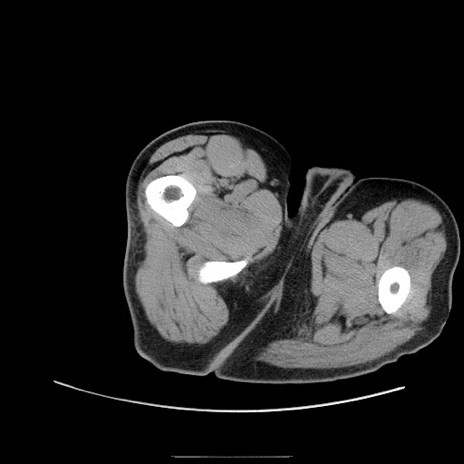

症例22(横断像)

【症例】50歳代男性

【主訴】腹痛

【現病歴】AVMからの被殻出血のため回復期リハ病棟入院中。 本日午後3時頃急に下腹部痛が出現した。

【既往歴】AVM、被殻出血、虫垂炎、高血圧

【身体所見】意識晴明、左半身不全麻痺、会話の理解は良好、36.5°C、腹部:膨隆、全体に板状硬、下腹部正中に圧痛点あり、反跳痛-、筋性防御不明、右下腹部にope scar

【データ】WBC 9400、CRP 0.06